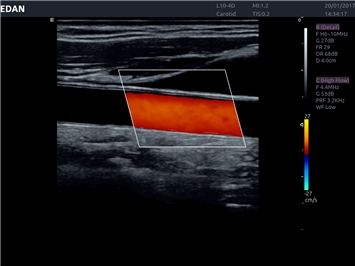

EDAN Acclarix LX4

Расширьте свои представления. Использование усовершенствованной платформой Acclarix система LX4 обеспечивает непревзойденную четкость изображений и интеллектуальный рабочий процесс для всех пользователей, являясь при этом наиболее экономичным решением.

EDAN Acclarix LX4 представляет собой инновационную ультразвуковую систему, построенную на усовершенствованной платформе Acclarix. Сочетание высокого качества визуализации с интеллектуальным рабочим процессом делает эту систему оптимальным выбором для клиник, ценящих эффективность и экономичность.

• Сосудистой диагностики

Цветовой допплер:

Да

Дуплексное сканирование: